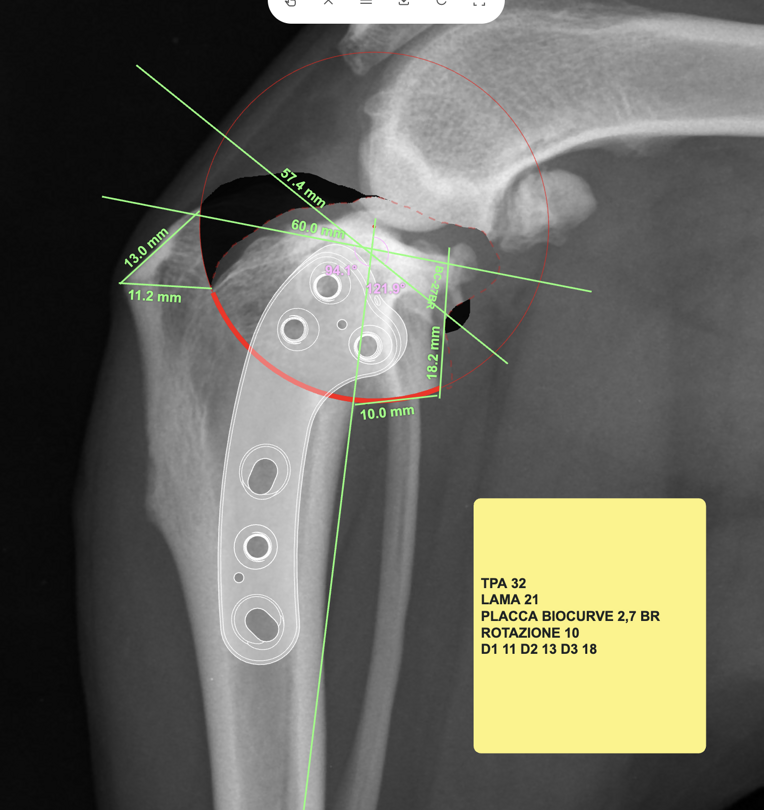

Quando necessario, il veterinario utilizza esami di imaging come le radiografie, utili per valutare ossa e articolazioni, oppure tecniche più avanzate come ecografie, TAC o risonanza magnetica, che consentono di studiare in modo più dettagliato tessuti molli, legamenti e strutture interne.